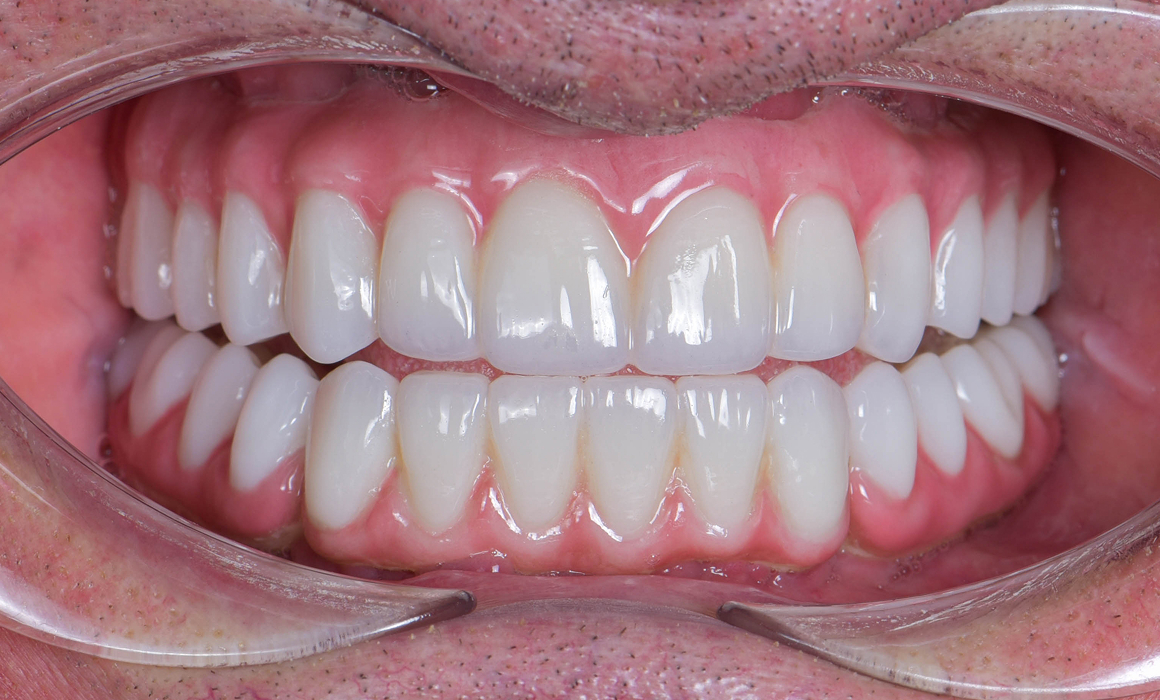

Улыбка до/после

Установка постоянного протеза

Через 4-6 месяцев после приживления имплантов, временные протез следует поменять на постоянный. Есть 2 вида финального протеза:

• Пластиковый. Более бюджетный протез, который следует менять каждые 3-5 лет. Стоимость 70.000 ₽

• Циркониевый. Постоянный керамический протез, который устанавливается на 15-20 лет. Стоимость 400.000 ₽

Циркониевый протез

• Высокая эстетика

• Срок службы 10-15 лет

• Хорошая прочность

Стоимость 400 000 ₽